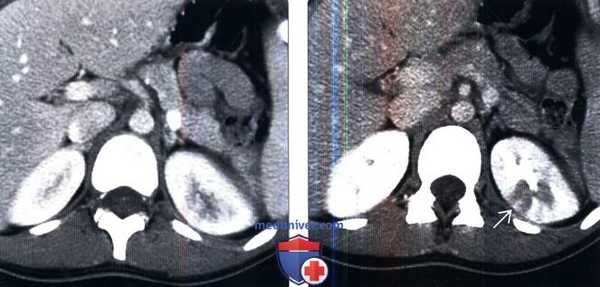

(Слева) КТ с контрастированием, аксиальная проекция, кортико-медуллярная фаза: аномалии левой почки не обнаружены.

(Справа) КТ с контрастированием, аксиальная проекция, экскреторная фаза: у этого пациента выявлено снижение перфузии верхнего полюса левой почки в связи с пиелонефритом.